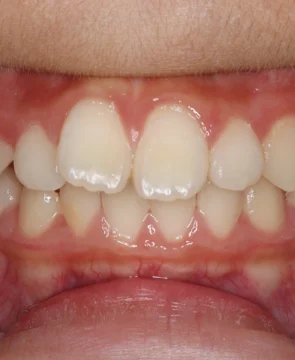

2026/04/14全体的な歯並びのがたつきが気になる10歳女児の矯正症例紹介 今回ご紹介する患者様は、全体的な歯並びのがたつきを気にされており、矯正検査後叢生Ⅰ級と診断いたしました。 治療前後の比較 矯正術前:正面 矯正術後:正面 矯正術前:右側 矯正術後:右側 矯正術前:左側 矯正術後:左側 矯正術前:上顎 矯正術後:上顎 矯正術前:下顎 矯正術後:下顎 矯正術前:前歯部あおり 矯正術後:前歯部あおり 矯正術前:オーバージェット 矯正術後:オーバージェット 主訴 全体的な歯並びのがたつきが気になる 治療期間 ・マウスピース矯正:10カ月 治療費用 …